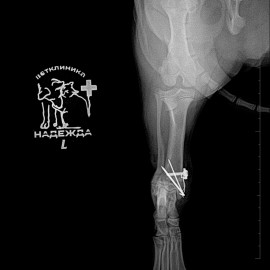

После осмотра и рентгенологического исследования был поставлен диагноз: перелом левой голени. Была проведена операция: остеосинтез левой голени.

Снимок 2-3 после операции.